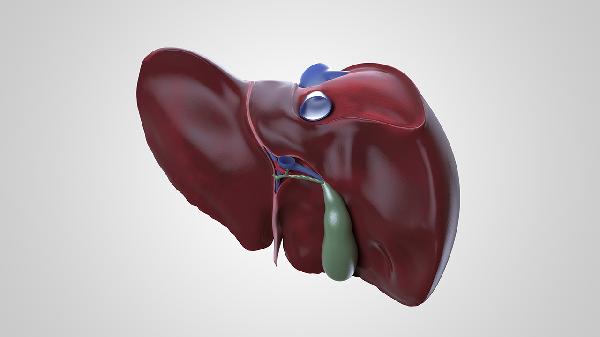

肝脏不健康的早期信号可能通过皮肤黄染、腹部胀痛、异常出血三个部位显现。肝脏作为代谢核心器官,其功能异常时可能出现黄疸、肝区隐痛、牙龈出血等症状,主要与病毒性肝炎、脂肪肝、肝硬化等疾病相关,建议出现相关症状时及时就医检查肝功能。

右上腹持续隐痛或胀满感可能与肝脏肿大相关,常见于脂肪肝、肝囊肿等疾病。疼痛可能放射至右肩背部,进食油腻食物后加重。建议完善CT或弹性成像检查,可遵医嘱使用复方甘草酸苷片、水飞蓟宾胶囊等护肝药物,日常需戒酒并控制体重。